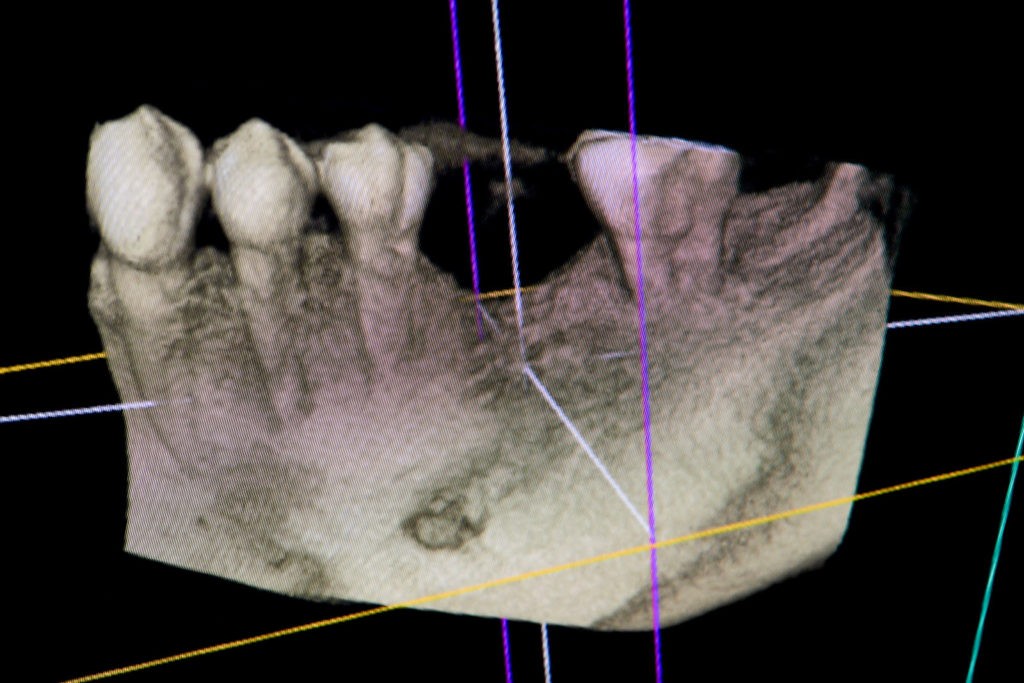

Przed podjęciem leczenia należy określić stopień zaniku kości szczęk oraz żuchwy. W tym celu przeprowadza się badanie kliniczne oraz odpowiednią diagnostykę obrazową pacjenta. Uwzględnia ona zdjęcie panoramiczne OPG jako podstawę dwuwymiarowego obrazowania podłoża kostnego oraz możliwe jest badanie tomograficzne CT lub bardziej precyzyjna tomografia stożkowa CBCT. Opcjonalnie wykorzystywana diagnostycznie tomografia pozwala na bardziej wnikliwą ocenę stopnia zaniku kości w trójwymiarowym, przestrzennym obrazie.

Precyzja projektu druku siatki bazuje na dokładności odwzorowania kształtu kości w stożkowej tomografii komputerowej CBCT, co zapewnia ich dobre przyleganie do podłoża kostnego oraz ogranicza powstawanie powikłań w postaci obnażania się siatek.